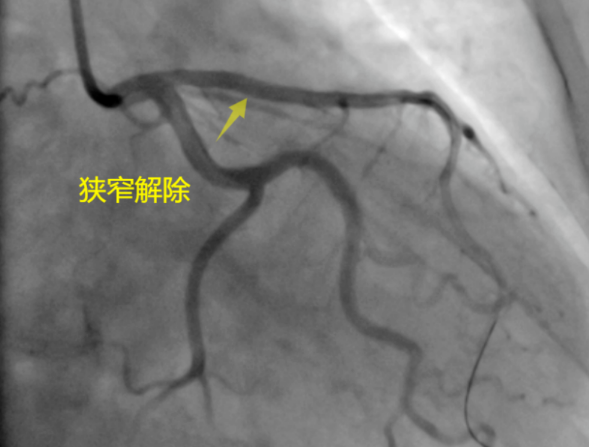

之后,大妈在燕化医院心内科进行了冠状动脉造影检查,发现她的三根冠状动脉中,有一根已经堵塞了95%。李钢主任亲自上阵,顺利地为大妈植入了“BioFreedom无聚合物载体药物涂层支架”。至此,笼罩在大妈一家困扰如风中的薄雾一般烟消云散了。